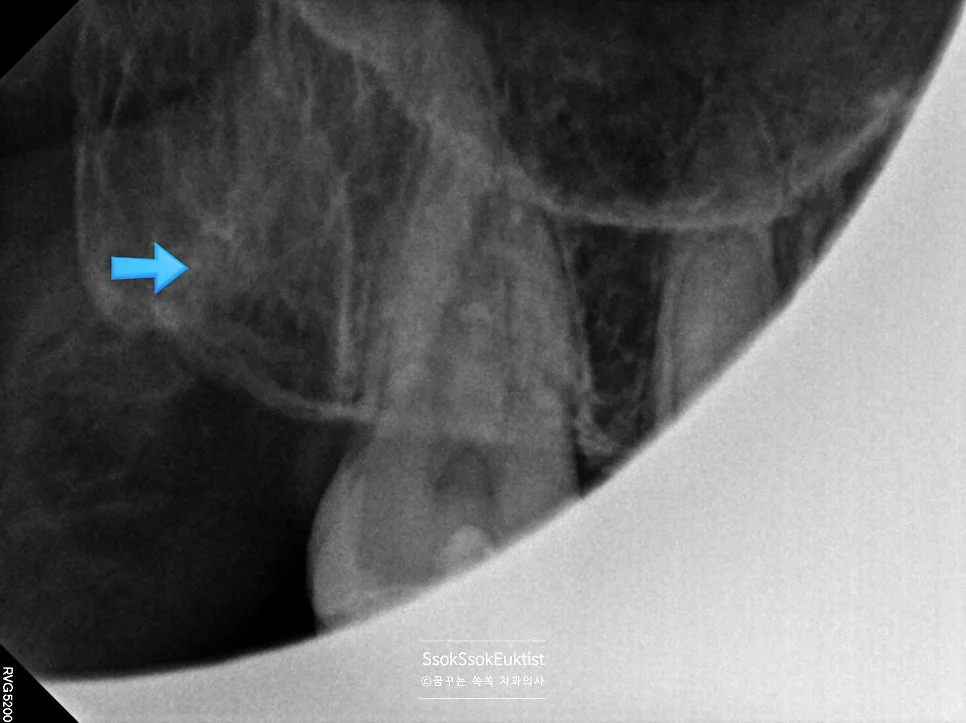

하악 매복 사랑니 충치 방사선 진단

하악 매복 사랑니 — 머리부터 충치가 진행된 상태

아래 두 개의 사랑니를 보면 머리부터 충치가 상당히 진행되어 있는 것을 볼 수 있습니다. 아래 사랑니는 매복 사랑니이기 때문에 발치를 해야 하고, 위 사랑니는 아래 사랑니를 제거하면 닿는 치아가 없어 필요 없고 관리만 안 되는 사랑니이기에 발치를 하는 것을 추천합니다!^^

매복 사랑니를 방치하면 바로 앞 치아에 충치 혹은 잇몸질환을 만들게 됩니다. 이것이 사랑니 발치를 꼭 해야 하는 가장 큰 이유입니다.

사랑니 인접 충치가 특히 위험한 이유

심지어 사랑니 때문에 생긴 충치는 치아 뿌리 쪽에서 시작하는 충치로, 뿌리를 구성하는 치아의 안쪽 재질(상아질)은 무르기 때문에 매우 빨리 충치가 진행하고, 심지어 거리도 신경과 매우 가깝기 때문에 조금만 방치하면 신경치료 및 크라운을 하게 됩니다ㅜ